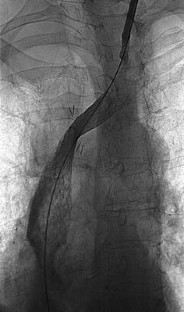

Treatment of Superior Vena Cava (SVC) Syndrome and Inferior Vena Cava (IVC) Thrombosis in a Patient with Colorectal Cancer: Combination of SVC Stenting and IVC Filter Placement to Palliate Symptoms and Pave the Way for Port Implantation

Thrombosis of the inferior vena cava is a life-threatening complication in cancer patients leading to pulmonary embolism. These patients can also be affected by superior vena cava syndrome causing dyspnea followed by trunk or extremity swelling. We report the case of a 61-year-old female suffering from an extended colorectal tumor who became affected by both of the mentioned complications. Due to thrombus formation within the right vena jugularis interna, thrombosis of the inferior vena cava, and superior vena cava syndrome, a combined interventional procedure via a left jugular access with stenting of the superior vena cava and filter placement into the inferior vena cava was performed As a consequence, relief of the patient’s symptoms, prevention of pulmonary embolism, and paving of the way for further venous chemotherapy were achieved.

Fig. 1